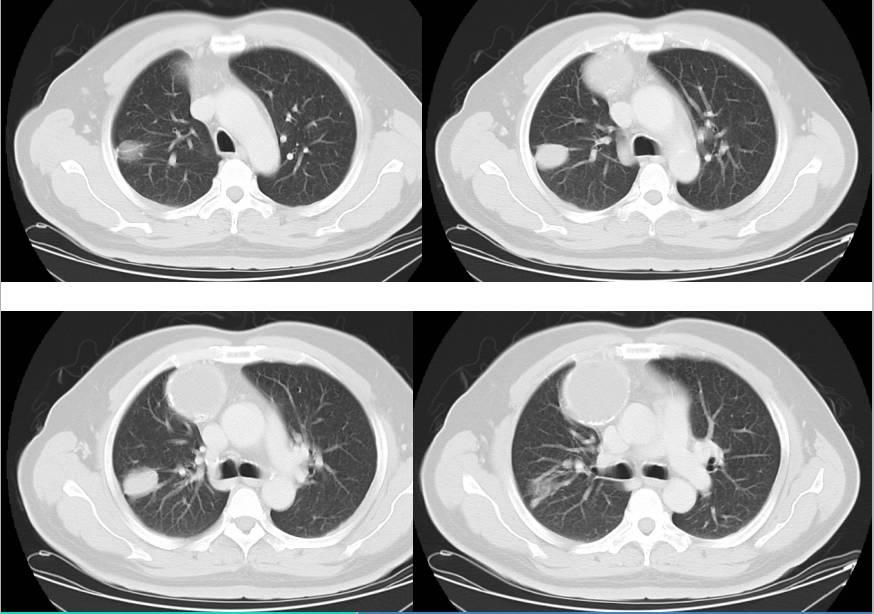

2、早期诊断技术:随着医学影像技术的不断发展,如超声、MRI等无创检查手段的普及,脂肪瘤的早期诊断率得到了显著提高,这些技术不仅可以帮助医生准确判断脂肪瘤的大小和位置,还可以评估其恶性转化的风险。